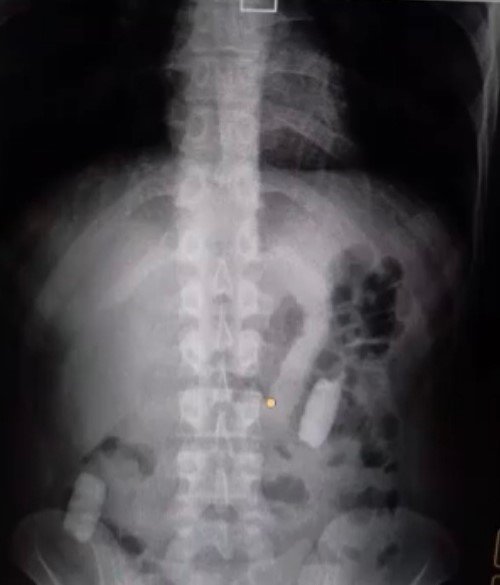

Kayseri İl Emniyet Müdürlüğü Narkotik Suçlarla Mücadele Şube Müdürlüğü ekipleri, uyuşturucu madde ticareti yapan şahıslara yönelik analiz çalışması yürüttü. M.R.B'nin (23) kente uyuşturucu madde getireceğini tespit eden ekipler operasyon düzenledi. Gözaltına alınan şahsın hastanedeki iç beden muayenesinde 77 adet kapsül şeklinde 1 kilo 134 gram narkotik madde ele geçirildi. Şahsın midesindeki maddeler cerrahi müdahale ile çıkarılırken, şahıs hakkında "uyuşturucu madde ticareti yapmak" suçundan adli işlem başlatıldı.